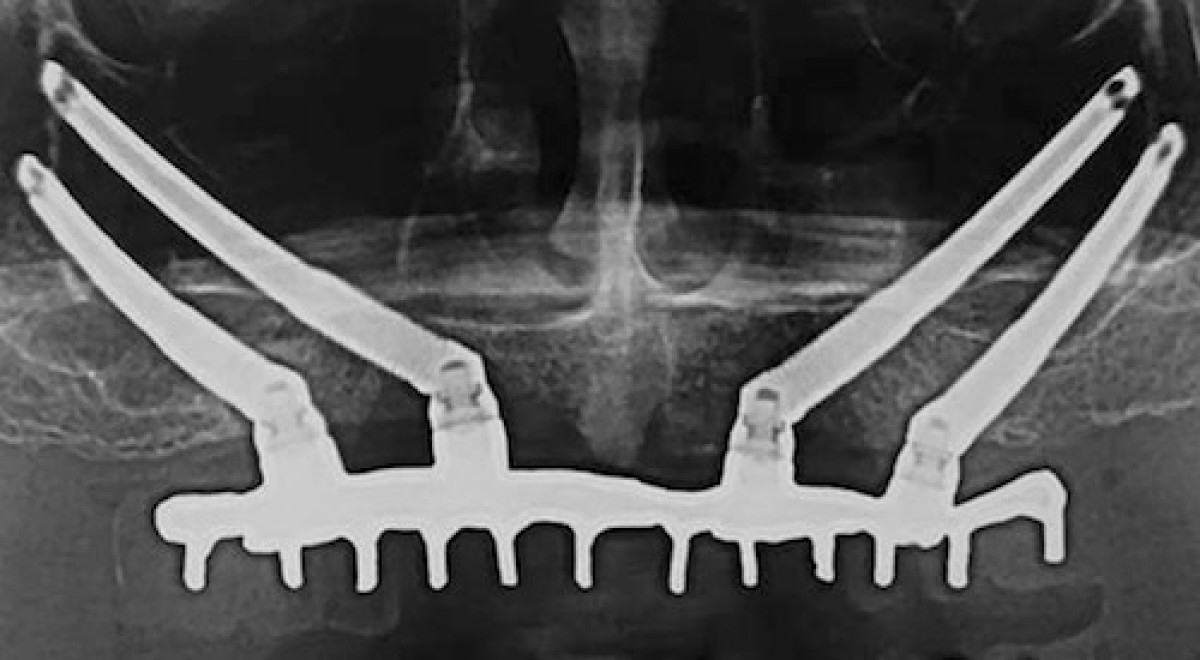

PURPOSE. To compare the clinical outcomes of immediately loaded cross-arch maxillary prostheses supported by zygomatic implants versus conventional implants placed in augmented bone.

Seventy-one edentulous patients with severely atrophic maxillae not having sufficient bone volumes for placing dental implants, or when it was possible to place only two implants of minimal diameter 3.5 mm and length of 8 mm in the frontal area and there was less than 4 mm of bone height subantrally were randomised according to a parallel-group design to receive either zygomatic implants (35 patients) to be loaded immediately or xenograft followed, after 6 months of graft consolidation, by placement of six to eight conventional dental implants submerged for 4 months (36 patients). Outcome measures were: prosthesis, implant and augmentation failures, any complications, quality of life (OHIP-14), number of days with totally or partially impaired activity, time to function, and number of dental visits, as assessed by independent assessors. Patients were followed up to 3 years after loading.

On the one hand, three-year post-loading data suggest that immediately loaded zygomatic implants are associated with fewer prosthesis failures (two versus eight patients), implant failures (three patients lost 6 zygomatic implants versus nine augmentation patients who lost 42 implants) and less time needed for functional loading (1.3 days versus 444.3 days) as compared to augmentation procedures and conventionally loaded dental implants. On the other hand, significantly more complications were reported for zygomatic implants; since there was an apparent increase in severe sinusitis at zygomatic implants over time, long-term data are required; however, in the short-term, zygomatic implants proved to be a better rehabilitation strategy for severely atrophic maxillae.